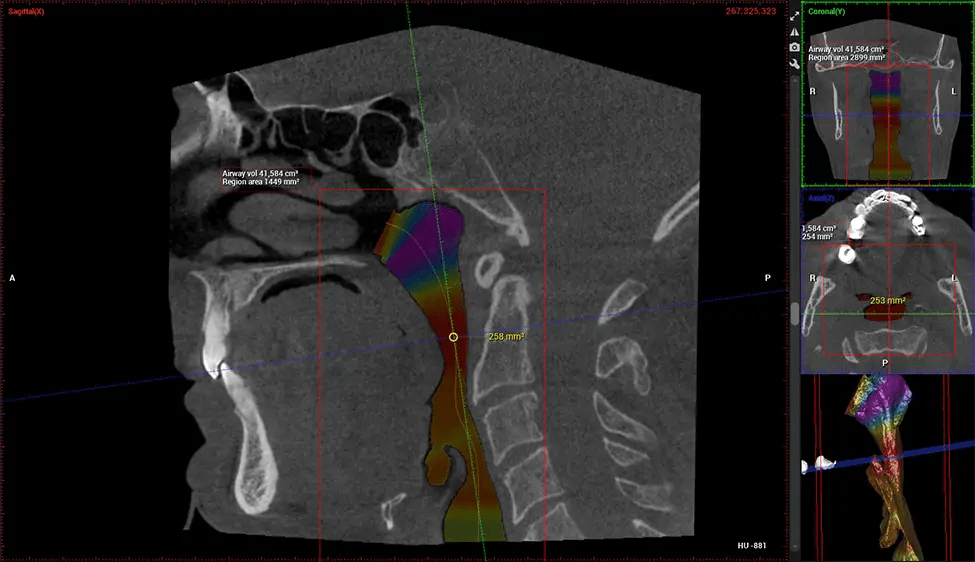

Esta exploración 3D, llamada tomografía computarizada de haz cónico, le brinda a su dentista una imagen más completa de su anatomía bucal y sus procesos patológicos que una radiografía tradicional. A diferencia de las radiografías convencionales, que capturan una imagen 2D de la boca desde varios ángulos, una exploración 3D toma varias radiografías digitales para una imagen. Proporciona una vista completa de la mandíbula, los dientes, los nervios y los tejidos blandos. Esta vista mejorada permite a los dentistas detectar problemas menores que no son visibles en las exploraciones 2D tradicionales, como muelas del juicio impactadas o fracturas óseas en la cavidad sinusal.

Existen muchos beneficios al utilizar la tecnología CBCT, especialmente en comparación con el formato tradicional de rayos X 2D. Una de las ventajas más importantes de las exploraciones CBCT es que proporcionan mucha más información que las radiografías tradicionales. Una exploración le permite a su dentista ver imágenes desde todos los ángulos de su mandíbula y boca, incluidos los senos nasales, la cavidad nasal, los pómulos y otras áreas circundantes. Esta información adicional ayuda a su dentista a elaborar un plan de tratamiento integral que aborde todos los aspectos de su salud bucal.

Otro beneficio importante es que las imágenes 3D proporcionan imágenes más precisas de la estructura ósea. Estas imágenes son más detalladas y le brindan un diagnóstico más preciso. Un diagnóstico preciso significa un mejor tratamiento para usted.

Después del proceso de escaneo, las imágenes de rayos X capturadas son procesadas por el software CBCT, que aplica algoritmos para reconstruir una imagen 3D detallada del área escaneada. El software recopila estas imágenes de rayos X individuales y crea una representación digital en 3D de la anatomía del paciente. El dentista o el radiólogo pueden ver y analizar la imagen CBCT 3D reconstruida. Esta imagen se puede manipular, rotar y acercar o alejar para examinar estructuras específicas y evaluar la condición del paciente.